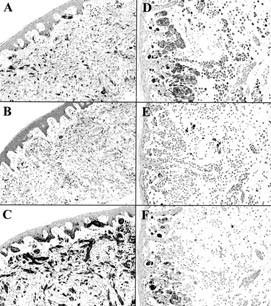

The staining of PNL2, anti–Melan A, and HMB-45 antibodies on paraffin embedded melanocytic tumors is detailed in Table 2. PNL2 immunostainings were very similar to those obtained with HMB-45. They were always strong with no background staining. About 90 to 100% of the melanocytes were labeled in all benign intraepidermal lesions, irrespective of their histologic type. As observed with HMB-45, common intradermal nevi and dermal component of compound nevi were largely non-reactive and only scattered nevus cells in the papillary dermis were labeled with PNL2 (Fig. 3), whereas anti–Melan A stained all melanocytes of the benign melanocytic lesions. However, spindle-shaped intradermal nevi such as blue nevus and desmoplastic Spitz nevus were consistently and strongly labeled by PNL2.

PNL2 immunostaining of benign melanocytic lesions, comparison with anti–Melan A and HMB-45 immunostaining. Left side: adjacent sections from a Spitz nevus. Whereas Melan A (A) and HMB-45 (B) stainings are heterogeneous, PNL2 (C) strongly stains all the cells of the nevus. Right side: adjacent sections from a compound nevus. Melan A is expressed by all the nevi cells (D), whereas the intradermal component of this nevus is largely non painted by HMB-45 (E), and PNL2 (F), with only scattered nevus cells labeled in the papillary dermis.